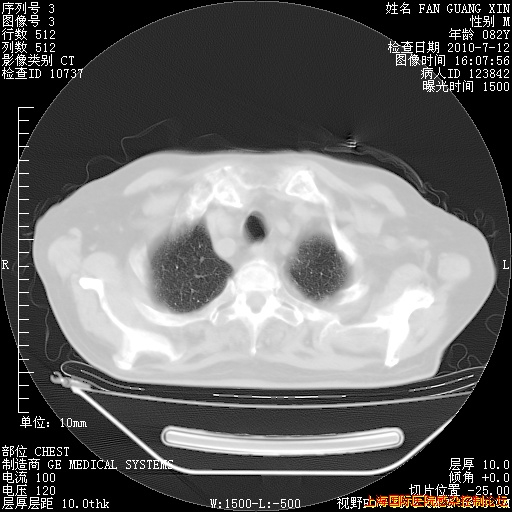

6月12日纵膈窗